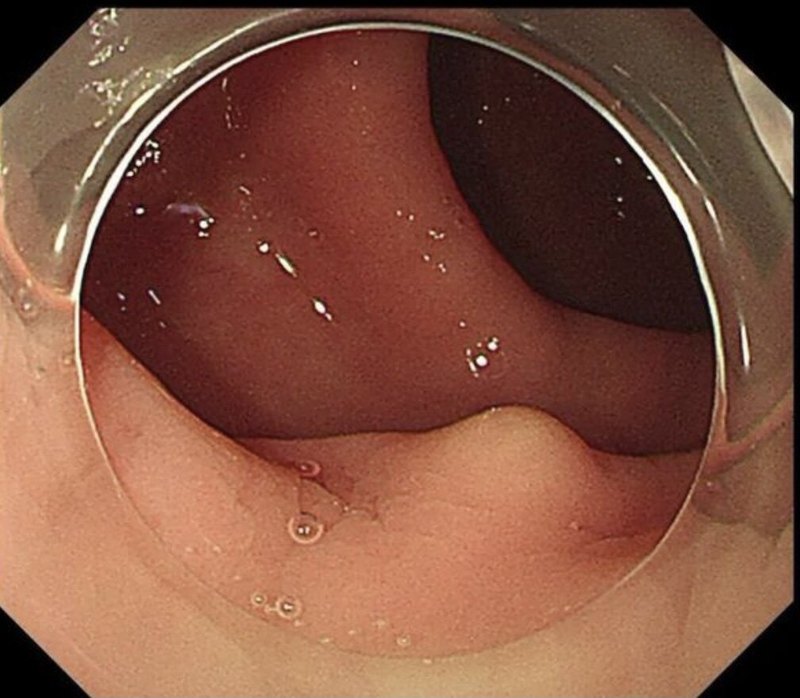

直腸類癌(直腸神經(jīng)內(nèi)分泌腫瘤)是發(fā)生于直腸黏膜上皮內(nèi)嗜銀細(xì)胞的腫瘤。直腸類癌臨床較少見,其發(fā)展緩慢,惡性程度較低,病情隱匿,早期常無(wú)明顯癥狀,臨床診斷較困難。起初在黏膜下有一個(gè)或數(shù)個(gè)結(jié)節(jié),質(zhì)硬、活動(dòng),表面光滑,長(zhǎng)到一定程度可穿破黏膜并發(fā)生轉(zhuǎn)移。瘤體直徑小于1厘米、無(wú)淋巴結(jié)轉(zhuǎn)移者行局部切除比較安全。 直腸類癌的病因目前仍不十分明確,其發(fā)病與社會(huì)環(huán)境、飲食習(xí)慣、遺傳因素等有關(guān)。直腸息肉也是本病的高危因素。 檢查 1.肛門指檢 可觸及黏膜下活動(dòng)、光滑、質(zhì)硬且界限清楚的腫塊。 2.結(jié)腸鏡檢查 結(jié)腸鏡下可見到有廣基息肉樣隆起,多為單發(fā),呈灰白色或黃色隆起型黏膜及黏膜下腫物,質(zhì)地硬,有完整的黏膜覆蓋。 3.直腸腔內(nèi)超聲檢查 對(duì)直腸類癌的診斷幫助較大,表現(xiàn)為黏膜內(nèi)低回聲圖形,橢圓形腫塊邊緣清晰,外形光滑,有助于確定患者有無(wú)局部淋巴結(jié)轉(zhuǎn)移。 4.病理檢查 因直腸類癌位于黏膜下,表面有正常的黏膜覆蓋,故做活檢應(yīng)取到黏膜下腫瘤組織才有價(jià)值。 診斷 1.直腸指診如果發(fā)現(xiàn)圓形、光滑的黏膜下硬結(jié),應(yīng)警惕本病。 2.結(jié)腸鏡及其活檢病理檢查是確診的主要方法。結(jié)腸鏡下典型表現(xiàn)為黏膜下結(jié)節(jié)狀隆起,直徑多小于1厘米,質(zhì)硬,推之??梢苿?dòng),表面黏膜光滑,顏色較蒼白發(fā)黃。病理活檢可確定腫瘤是惡性還是良性。 治療 1.直徑